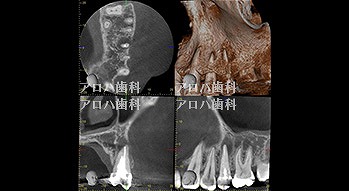

case8

自費の補綴

頬側に瘻孔

case9

遠心口蓋側に限局性の深いポケット

上顎洞に波及している。